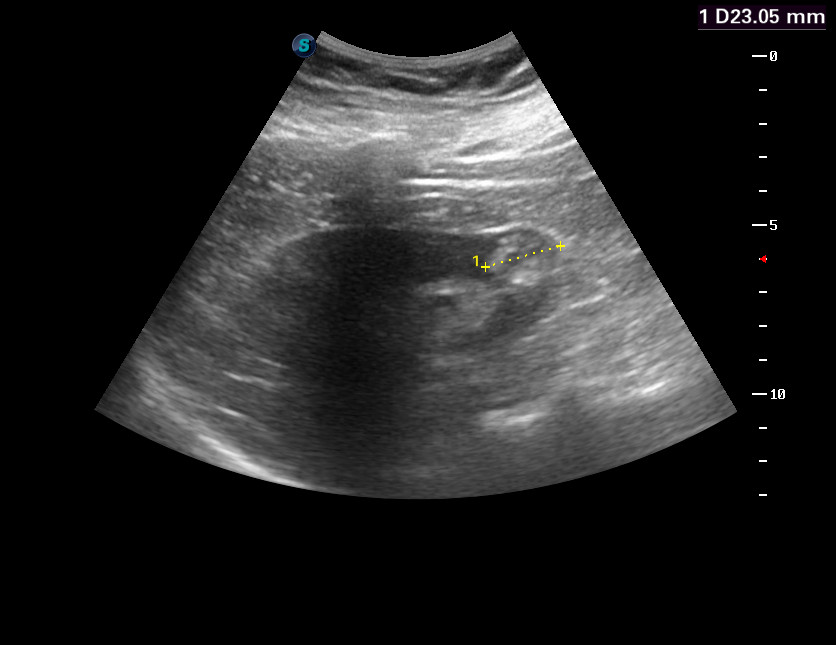

Женщина 55 лет, жалоб нет.

В нижнем полюсе правой почки обнаружено такое образование.

Немного похоже на AML, но неоднородное по структуре и с внутренним кровотоком, характеристики которого не в пользу RCC. Нет гипоэхогенного ободка, как при RCC.

Выполнена КТ с контрастированием.